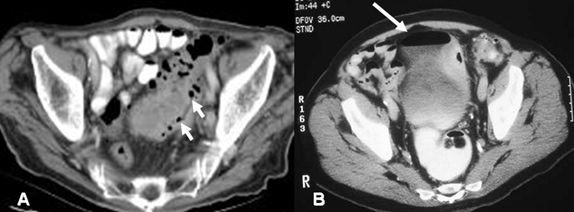

Η αξονική τομογραφία κοιλίας και πυέλου είναι η πλέον κατάλληλη και παθογνωμονική απεικονιστική εξέταση για τη διάγνωση της οξείας εκκολπωματίτιδας (Εικόνα 4).

Εικόνα 4.

Ευρήματα εκκολπωματίτιδας στην αξονική τομογραφία:

Α. Εκκολπώματα (μικρά βέλη), πάχυνση τοιχώματος και ελάττωση εύρους του αυλού του παχέος εντέρου.

Β. Παρουσία αέρα μέσα στην ουροδόχο κύστη (μεγάλο βέλος) από κολοκυστικό συρίγγιο